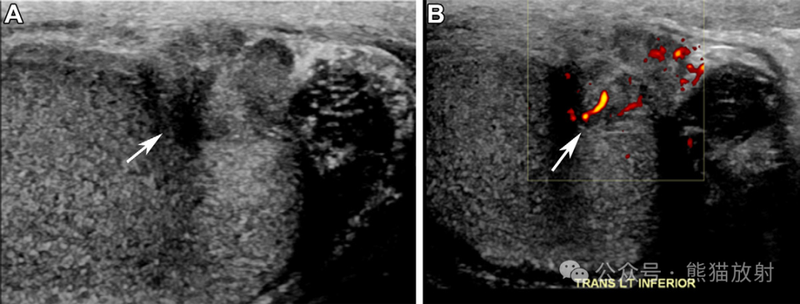

57岁男性,睾丸鞘膜间皮瘤。阴囊的灰度 (A) 和彩色多普勒 (B) US图像显示睾丸旁不均质回声病变(A箭),血流增加(B箭)。